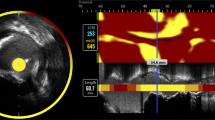

Carotid endarterectomy (CEA) surgery was performed by carefully opening the outer wall of the carotid artery and excising the plaque by separating the intima and media. This protocol preserves an intact lumen and plaque morphology [21]. Two human carotid plaque specimens, harvested at carotid endarterectomy (CEA) surgery, were rinsed in phosphate-buffered saline (DPBS), snap frozen and stored at − 80 °C until further processing. A third carotid artery specimen, without apparent atherosclerotic disease, was collected at autopsy within 24 h postmortem, from a subject with a non-cardiovascular cause of death. This specimen was rinsed in DPBS and stored in the same manner. Tissue collection was performed according to protocols sanctioned by the Ethics Board at Erasmus MC (MEC 2008-147 for carotid endarterectomy samples, MEC 2017-300 for the autopsy sample).

One CEA specimen, referred to as P1, was transversally divided into 1-mm segments to study intraplaque variability. We hypothesize that the plaque’s molecular lipid composition may change along the length of the vessel. Five 1-mm segments, originating ≈ 3 mm apart, evenly spaced along the axial length of the CEA sample, were used for imaging. Three of the segments were located caudal to the carotid bifurcation and two segments originated from the internal carotid artery, see Figure 1. The second CEA specimen, referred to as P2, and the autopsy specimen, referred to as A, were imaged in a single axial location. The imaged 1 mm segment of P2 was located cranial to the bifurcation, in the internal carotid artery, where atherosclerotic disease stage is generally maximal. The imaged 1 mm segment of A originated from the common carotid artery, where no or minimal plaque formation is expected.

We assessed the plaque tissue according to the plaque classification scheme of Virmani et al. [2, 3] and examined the tissue for features of plaque vulnerability (i.e., necrotic core, calcification, thrombus). We also assessed the tissue’s structural variability over consecutive tissue sections that originate from the same 1 mm segment. We used the histopathological data as a guidance to interpret the MALDI-MSI data.

Segment P1–4 contained thrombus; see Figure 7c, in which monoacylglycerols (MAG), diacylglycerols (DAG), and triacylglycerols (TAG) were abundantly present. When we compared 300 × 300 μm regions of interest (ROIs) in tissue segments, we found the DAGs to be more abundant in the thrombus region of P1–4 compared to another region in the same segment and also compared to other segments and other tissue samples. As such, a high concentration of DAGs appears to be thrombus-specific. In Figure 7, an example of the distribution and intensity of DAG 34:2 is shown, in comparison to the other tissue sections measured. In the supplementary information C, a list of all peaks assigned as DAGs with distributions similar to DAG 34:2 are given.

Distribution of diacylglycerol (DAG) 34:2 (m/z 575.51). (a) Boxplot of average intensity of diacylglycerol (DAG 34:2, [M + H-H2O]+) in a 300 × 300-μm region of interest in tissue segments. Expression in the thrombus-containing ROI of segment P1–4 (P1–4 Thr) is highly elevated. (b) MALDI MSI of P1 segment 1 and 4. The thrombus region is outlined in cyan. (c) ORO staining of MALDI section and HE staining of adjacent section indicating thrombus